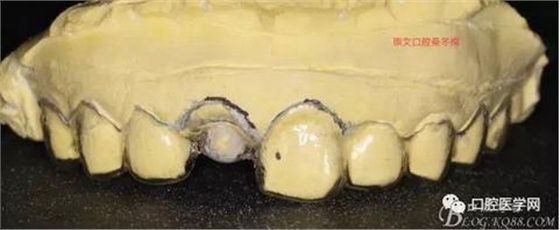

制作導(dǎo)板

戴入導(dǎo)板